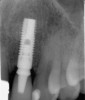

Figure 2  Identification of sufficient inter-radicular space: The radiographic representation of inter-radicular space (Fig 2) reveals abundant space for a single-tooth implant; at the alveolar crest, > 6 mm of interproximal space is available for placement of a 4-mm implant without encroaching on bone and periodontal ligament at the adjacent teeth. The 5-year-follow-up radiograph (Fig 3) reveals the interproximal maintenance of bone at this implant/abutment interface and adjacent teeth, in part due to proper planning and implant placement.

Figure 3  Identification of sufficient inter-radicular space: The radiographic representation of inter-radicular space (Fig 2) reveals abundant space for a single-tooth implant; at the alveolar crest, > 6 mm of interproximal space is available for placement of a 4-mm implant without encroaching on bone and periodontal ligament at the adjacent teeth. The 5-year-follow-up radiograph (Fig 3) reveals the interproximal maintenance of bone at this implant/abutment interface and adjacent teeth, in part due to proper planning and implant placement.

Figure 3